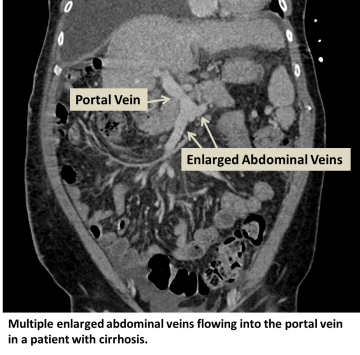

Portal hypertension is increased blood pressure in the portal venous system, a system of veins draining the abdominal organs into the portal vein, which then drains into the liver. Portal hypertension can result in blood backing up into various abdominal organs, such as the spleen, esophagus, and rectum with resultant bleeding.

Portal hypertension can be caused by anything that limits blood flow through the portal vein, through the hepatic veins draining the liver, or through the liver itself. As a result, pressure builds up in the portal system. Examples of conditions that can cause portal hypertension include portal vein clots, liver disease, and right heart failure. The most common cause of portal hypertension is chronic liver scarring called cirrhosis.

Multiple enlarged abdominal veins flowing into the portal vein in a patient with cirrhosis.